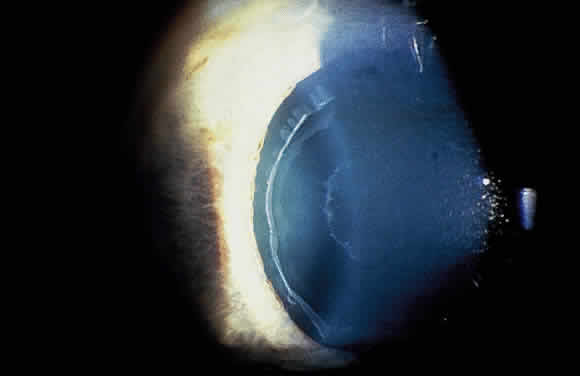

Deposition of exfoliative material on the anterior lens surface is the most commonly recognized feature of XFS and usually is best appreciated after pupillary dilation.43 A bull's-eye pattern generally is seen in which a translucent central zone and a granular peripheral zone of deposition are separated by an intermediate clear zone (Fig. 1). The translucent central zone of exfoliative material varies in diameter and may exhibit curled edges. In approximately 20% of patients with exfoliation, the central zone may be absent.38 The intermediate clear zone presumably results from lens contact with movement of the iris. The granular peripheral zone, which may be subtle but invariably is present in XFS, generally exhibits a well-delineated inner border and often shows numerous radial striations (Fig. 2). Occasionally, a bridge of exfoliative material may cross the clear zone to join the central zone and the granular peripheral zone.38,44